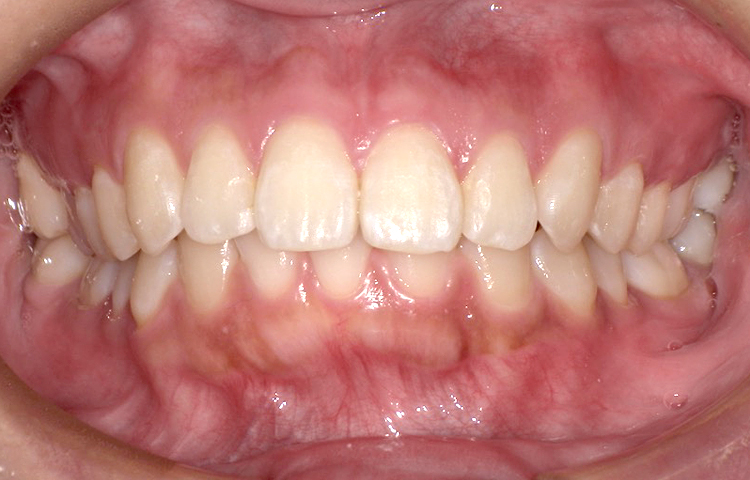

症例3

治療前

治療後

| 主訴 | 上下前歯全体の歯並びが気になる |

|---|---|

| 治療 期間 |

約6ヶ月 |

| 治療費 | 330,000円(税込)/調整費用別途 |

| 治療 内容 |

上下の前歯部にワイヤーを着けて進めていく、プチ矯正で施術。 |

| 治療の リスク |

固定の装置をつけないと後戻りしてしまう。 |